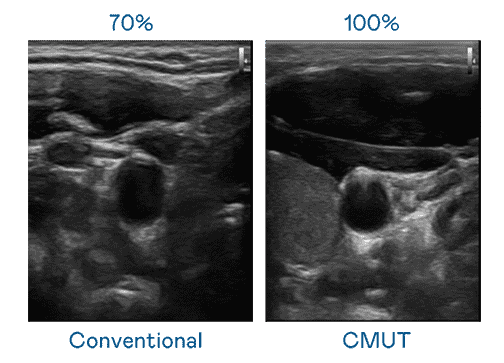

CMUT 技术是一种用电容式微机电元件来产生超音波讯号的技术。。。与传统 PZT 压电式技术相比,,,,CMUT 频宽增加 30%,,更宽频的超音波讯号让影像解析度大幅提升,,,是实现高影像品质医疗超音波扫描、、、促进精准医疗发展的关键技术。。。。

大频宽带来超清晰影像

超音波影像的解析度高低,,首先取决于探头能发出的讯号频宽。。z6尊龙 CMUT 可提供高清晰的超音波讯号,,,提供高频宽、、、高灵敏度、、、、影像纹理细节更高的超音波影像,,,协助医护人员缩短影像判读时间及利用精准的医疗影像进行诊断。。。